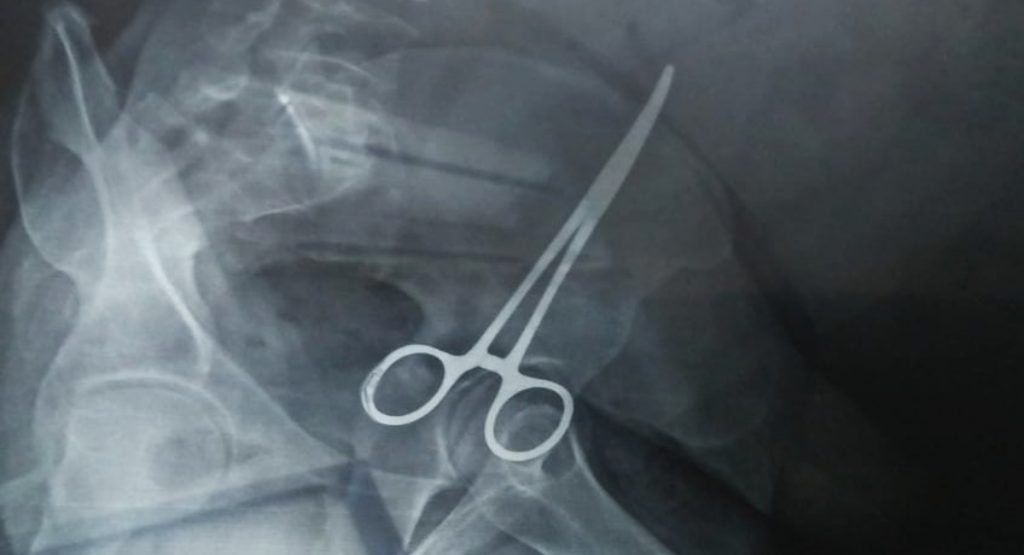

22 मार्च को पेट में कैंची होने का पता चला

बेगम की हालत में सुधार नहीं होता देख शौहर असलम ने भागलपुर के ही डॉ राजन कुमार सिन्हा के क्लिनिक में दिखाया, जहां एक्स-रे और अन्य जांच के दौरान पता चला कि पीड़िता के पेट में कैंची है. यह कैंची 11 वर्ष पूर्व पीड़िता के प्रसव के वक्त डॉ सुरेश प्रसाद के निजी क्लिनिक में ऑपरेशन के दौरान लापरवाही बरतते हुए छोड़ दिया गया था. पेट में कैंची की बात सुनते ही सभी पर दुखों का पहाड़ टूट गया. भागलपुर के चिकित्सक ने हाथ खड़े कर दिये. अब इलाज के लिए पटना जाना होगा. इस बाबत जब डॉ सुरेश कुमार से 8 अप्रैल को पीड़िता और असलम शिकायत करने पहुंचे, तो उनलोगों के साथ अभद्र व्यवहार किया गया. विरोध करने पर अज्ञात व्यक्ति के साथ मारपीट पर उतारू हो गये. यही नहीं, 50 हजार का प्रलोभन भी दिया जा रहा है कि वह चिकित्सक का पीछा छोड़ दे.